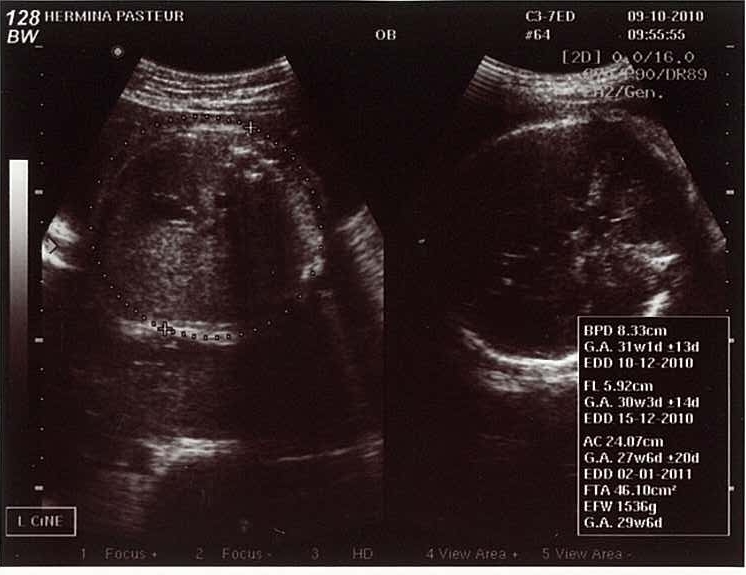

USG 9 Minggu - YouTube Hamil 2 Bulan: Dari Embrio Menjadi Janin - Alodokter USG Kehamilan 9 Minggu | Alhamdulilah Sehat | Ita Rosida - YouTube Kenali Cara Membaca Hasil USG Untuk Tahu Kondisi Bayi - Ibupedia Cara Membaca Hasil USG yang Benar, Wajib Tahu! 9 minggu alhmdulillah detak jantung udh kedengern,, - IbuHamil.com Ketahui Tumbuh-Kembang Anak Selama Kehamilan - Kompasiana.com Manfaat USG untuk Ibu Hamil dan Janin - Ibupedia Perkembangan Janin di Minggu ke-9 Sampai ke-12 Kehamilan USG bayi 2 dimensi usia 9 minggu - YouTube Ternyata Cukup 3 Kali Melakukan USG Selama Kehamilan, Ini Penjelasannya, Moms! Nanda Novita Hertanti :.: June 2013 Netizen Peringatkan Shandy Aulia Karena USG Tiap Minggu, Bahayakah? hamil 9 minggu . Perkembangan Kehamilan Usia 9 Minggu - Mamapapa.id % USG Kehamilan, Penting gak sih ? | Ikhsan Kurniawan BILIK SONOGRAFER : Kehamilan Awal (Kehamilan Trimester 1) JANIN BELUM TERLIHAT SAAT USG? JANGAN KHAWATIR, MOMS! - susistory USG usia 9 minggu ny Lilis “RS.Hermina Galaxy” - YouTube bentuk USG janin 9w - IbuHamil.com Hamil Kosong Atau Blighted Ovum (BO) – . Perkembangan Janin Usia 9 Minggu - Bidanku.com Setelah USG Dokter Memvonis Kehamilan Kosong, Ini Sebabnya - Tribun Jambi Penantian 9 Tahun Berbuah Manis, Rianti Cartwright Akhirnya Hamil Anak Pertama - Semua Halaman - Grid.ID USG 4D Diusia Kehamilan 38 Minggu | Laci Ajaib Blighted Ovum, Kehamilan Tanpa Janin - Medianers Berapa Kali USG Saat Hamil Harus Dilakukan? Diary Kehamilan: Cerita Kehamilan Pertama, Pertama Tahu Hamil – ranselriri Ibu Hamil, Ini 12 Tandanya Bayi di Dalam Kandunganmu Sehat | BukaReview USG 9 Minggu 5 Hari - YouTube Hasil USG Umur Janin 9 Minggu | Our family home’s Blog Kapan Denyut Jantung Janin Bisa Terdeteksi? | HonestDocs 10 Tanda Tanda Hamil Kosong - Penyebab, Perawatan dan Pencegahan - Hamil .co.id USG Janin 9 minggu (Perkembangan Awal Kehamilan ) brg dr. Dian Indah Purnama di RS Bunda Margonda - YouTube Blighted Ovum, Kehamilan Tanpa Janin - Medianers Cara Membaca Hasil USG yang Benar, Wajib Tahu! Gambaran Hasil Usg Kehamilan 5 Minggu Yang Perlu Diperhatikan - Hamil.co.id Bagaimana Cara Membaca Hasil USG? • Hello Sehat Syahnaz Sadiqah Hamil 8 Minggu, Hasil USG Tunjukkan Dua Janin Sekaligus - Tribun Pontianak Ketahui Tumbuh-Kembang Anak Selama Kehamilan - Kompasiana.com Thanks, God! It’s sooooo amazing… | Selamat Datang di Istana Putri !!! USG 4 Dimensi Tidak Diperlukan Ibu Hamil? - Health Liputan6.com Perkembangan Janin Usia 9 Minggu Perkembangan janin 9 minggu - Panduan untuk ibu hamil | theAsianparent Indonesia My Pregnancy Journey - trimiyati yuliana USG untuk Pemeriksaan Kehamilan 2 Bulan ~ DOKTER OZ INDONESIA 26 Februari 2017 - YouTube Kesalahan Memprediksi Jenis Kelamin Saat Awal Kehamilan - kumparan.com USG dasar dalam kehamilan Kapan Ibu Hamil Mulai Merasakan Gerakan Janin? - kumparan.com Perkembangan janin 9 minggu - Panduan untuk ibu hamil | theAsianparent Indonesia Memasuki Hamil 9 Minggu, Apa Saja yang Terjadi? Viral, Rekaman USG Bayi Kembar Bertengkar dalam Rahim - Citizen6 Liputan6.com Memahami Air Ketuban dan Fungsinya - Alodokter Pertambahan Berat Janin Normal di Tiap Trimester Kehamilan FOTO: Hamil 10 Minggu, Rinni Wulandari Pamer Hasil USG : Okezone Celebrity Pengalaman Umrah Saat Hamil 9 Minggu - A Cup of Coffee SYOK! Dokter Kandungan Ini Kaget Lihat Hasil USG Ibu Hamil, Mencengangkan! - Halaman all - Tribun Manado Cara Membaca Foto USG: 8 Langkah (dengan Gambar) - wikiHow Dokter ketiga dalam kehamilan 9 minggu - IbuHamil.com Kapan Kehamilan Kembar Terdeteksi USG 4 Dimensi di Bandar Lampung - Info Bandar Lampung Ciri-ciri Hamil dengan Kondisi Janin Tidak Berkembang - kumparan.com Retno A Twitter: “@falla_adinda teh ini USG usia 9 minggu. Itu kepalanya kok udh dbawah ya kayakny? Eh iya gak sih? Belum USG lg soalny http://t.co/o6l2Jw7lsK” Cara Membaca Foto USG: 8 Langkah (dengan Gambar) - wikiHow Pengalaman Hamil Kembar - The Urban Mama Bumil Wajib Tahu, Inilah Penyebab Bayi Sungsang dan Cara Mengatasinya Sedang hamil, ini 10 foto USG yang kerap dipamerkan Shandy Aulia CeRiTa cHa: Para Ibu Hamil, Ini Keluhan yang Biasanya Muncul Saat Tri Semester Pertama Kehamilan Kehamilan 9 Minggu Janin 7 Minggu Jumlah Bayi Kembar yang Lahir Tak Sesuai Hasil USG? Ini Penjelasan Dokter 5 Langkah Membaca Hasil USG yang Bisa Bunda Pelajari Evan Reisha - Kontrol Kandungan Ke-6 (Trimester 2-3, 27W6D) Inilah Alasan Ibu Hamil Perlu Melakukan USG Kehamilan Perkembangan Janin 3 bulan / 12 minggu USG - Cerita kehamilanku part 3 - YouTube MND Clinic Instagram posts - Gramho.com usg hamil 9 minggu Rachel Maryam Hamil Anak Kedua di Usia 40 | Merdeka.com | LINE TODAY Sedang hamil, ini 10 foto USG yang kerap dipamerkan Shandy Aulia Mulai Rasakan Mual, Ini 6 Momen Zaskia Sungkar Cek USG Janin Pertama Kali Ternyata Positif Sedang Hamil Kembar-Keluarga si Kembar Ternyata Seperti Ini Berat Janin 3 Minggu di Awal Kehamilan dan Perkembangan yang Dialaminya - Semua Halaman - Nakita USG dasar dalam kehamilan Informasi Lengkap Perkembangan Janin dan Ibu Hamil Minggu ke-9 "Down Syndrome" Terdeteksi Lewat USG 3 Kemungkinan Penyebab Janin Tidak Terlihat di USG Diari Kehamilan Pertama: Kontrol Kandungan Ke-2 (Trimester 1, 7W6D) 10 Manfaat USG Kehamilan Bagi Janin - Hamil.co.id Hasil USG | Febriyan Indriana 31w3d pregnancy… - The Daily Rella Janin Usia Kandungan 12 Minggu Hamil USG 9 Minggu 5 hari. Deg2an janinnya berkembang atau tidak - YouTube Banyak Fungsi, Tak Hanya untuk Cek Jenis Kelamin Mengenal Peranan USG Dalam Kehamilan Selamat! Rachel Maryam Tengah Mengandung 12 Minggu, Bahagia Bagikan Perkembangan Janin - Tribunnewsmaker.com Diary Kehamilan: USG 4D Murah Meriah – ranselriri Mengetahui Usia Kehamilan Dengan USG – . Mengenal Kehamilan Kosong atau Blighted Ovum (BO) - Bidanku.com 3 Cara Membaca Hasil USG yang Benar, Biar Nggak Salah Kaprah | merdeka.com Atiqah Hasiholan Hamil 7 Bulan, Rio Dewanto Berbagi Hasil USG - Kapanlagi.com Ini Waktu Yang Ideal Untuk Melakukan USG 4 Dimensi Saat Hamil - Semua Halaman - Nakita Hasil USG Kehamilan 24 Minggu : “Istriku Hamil Mobil Sport!” | theAsianparent Indonesia